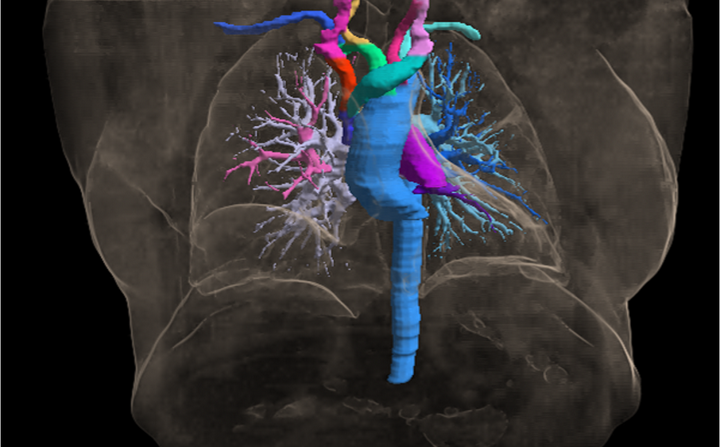

胸腔血管三维可视化

飞标平台借助医学影像分割大模型MISM进行了全新升级,4.0版实现了通过一个点、一个边界框,一键分割出病灶或解剖结构的功能,能够更精准的连续逐层标注。此外,飞标4.0版支持集成第三方的预标注算法,使飞标平台具有了功能可扩展的开放性。

5、高级可视化,提高标注效率和准确率——通过大量的基于web的三维可视化技术,让使用者从二维标注扩展到全面了解病变情况的三维环境,并提供基于三维立体交互式分割技术,让标注更智能。